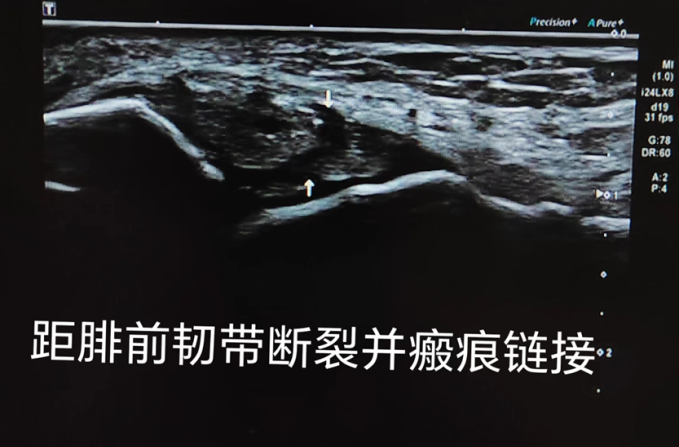

以上是距腓前韧带各种损伤超声表现

精准诊断:在踝关节轻度扭伤时,肌骨超声可以观察到韧带增厚水肿、松弛;在踝关节严重扭伤时,肌骨超声可以观察到韧带撕裂、完全断裂、周围骨质撕脱骨折等情况。通过肌骨超声检查,医生可以准确地判断韧带损伤的程度,为制定治疗方案提供重要的依据。